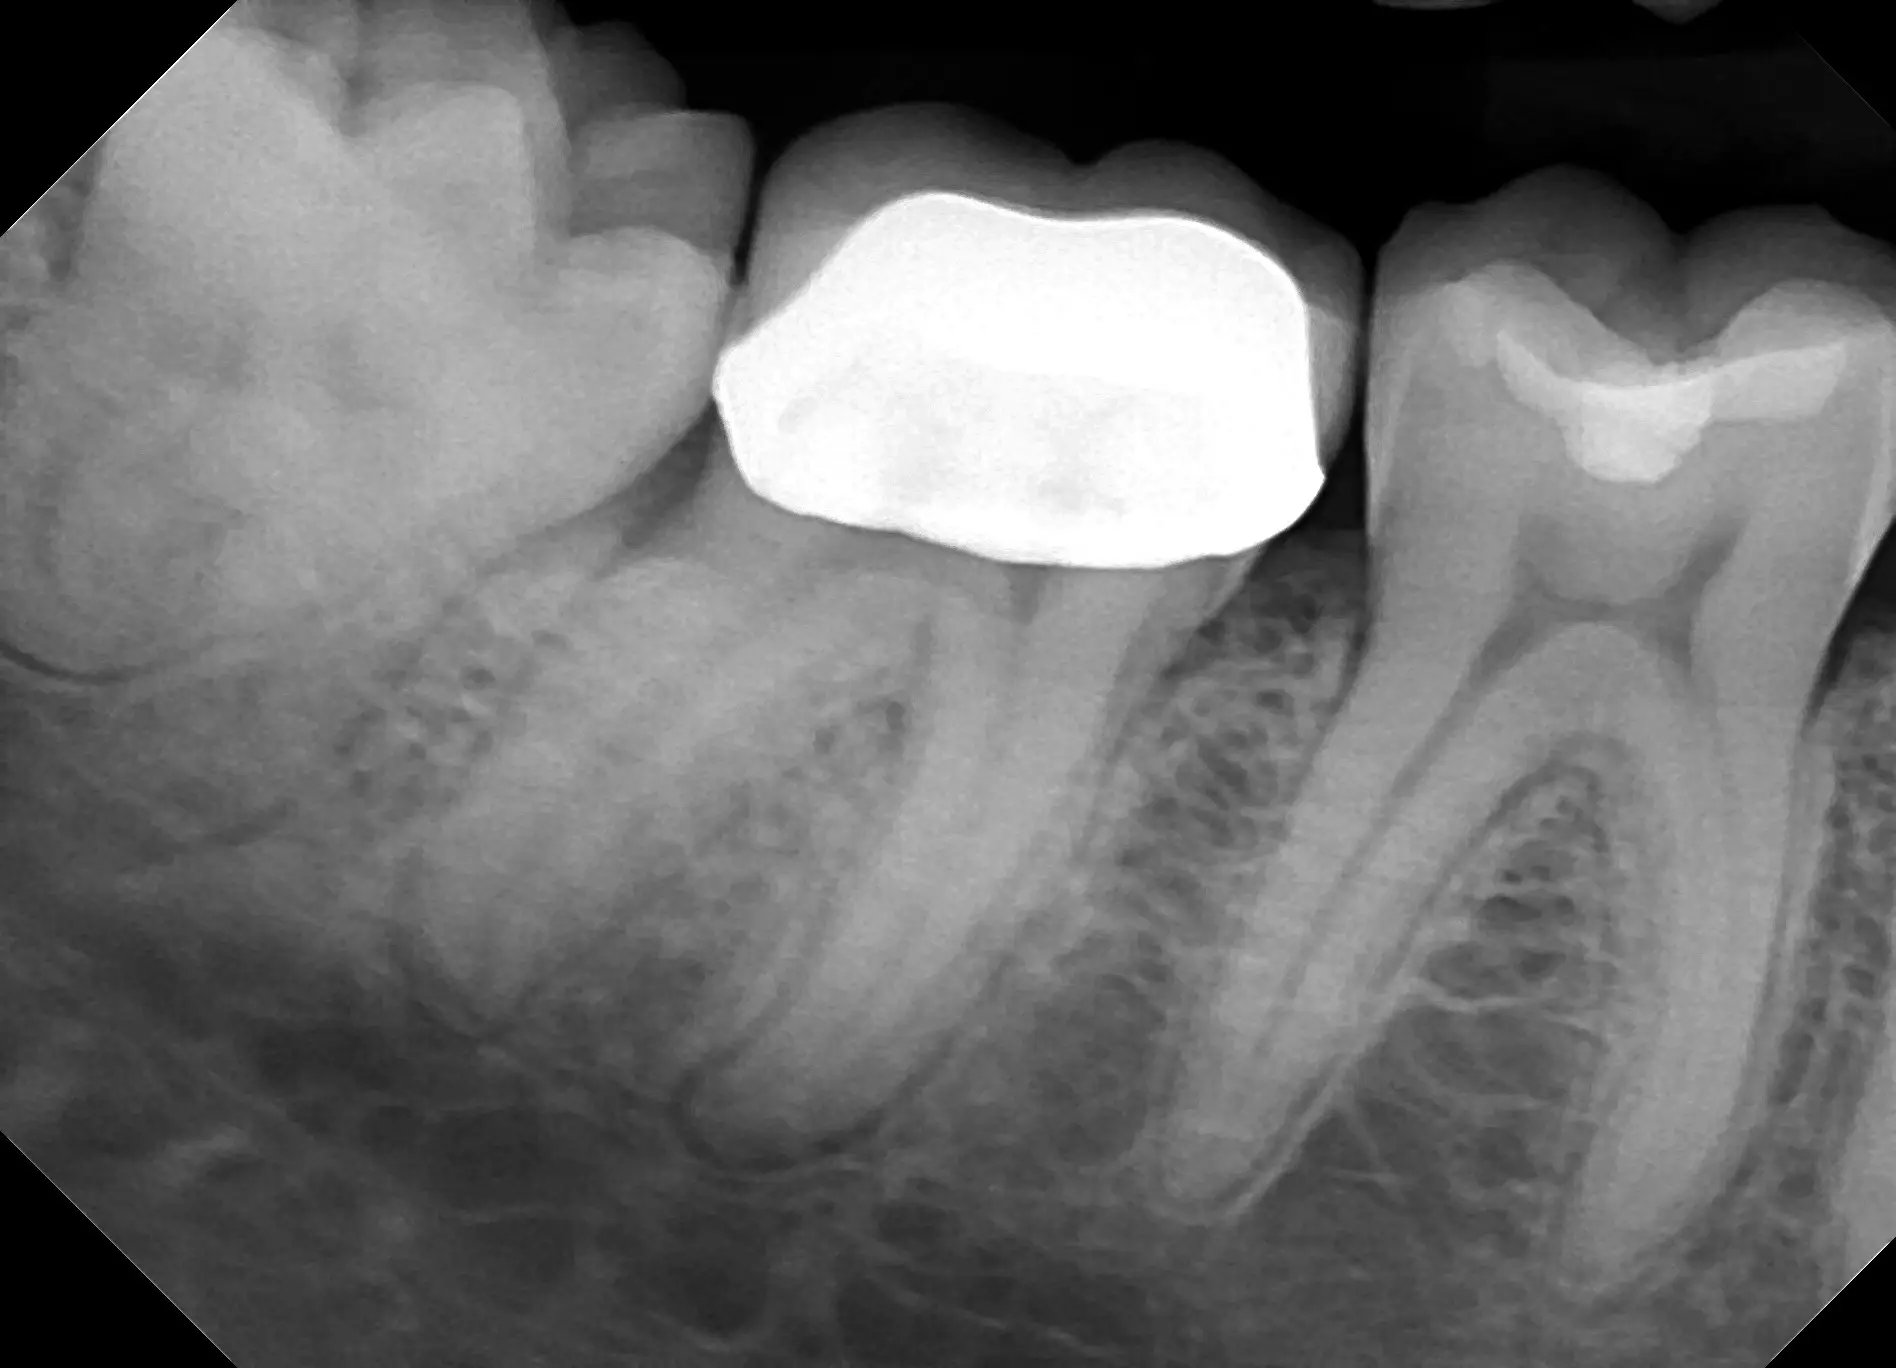

See for yourself the X-ray Gallery from the Dream Sensor!

Click any image in the x-ray gallery below to see the full version.

All images are taken with the DentiMax Dream Sensor and are compatible with the DentiMax Imaging Software and most other imaging software on the market.